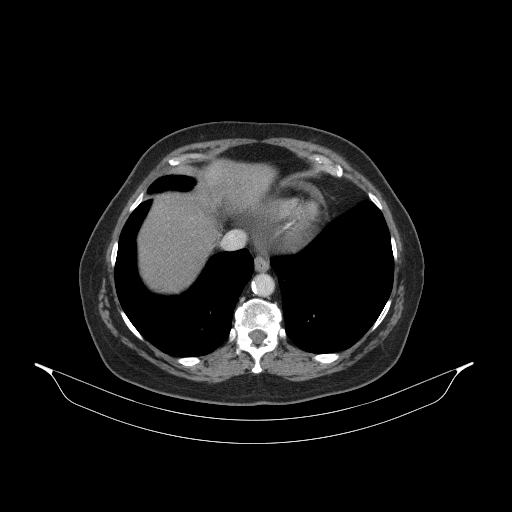

Generated VENOUS CT scan (A→B translation)

Full window (WL 1023.5, WW 4095 β†’ Low βˆ’1024, High +3071)

Actual HU range: [-1024.0, 1197.0]